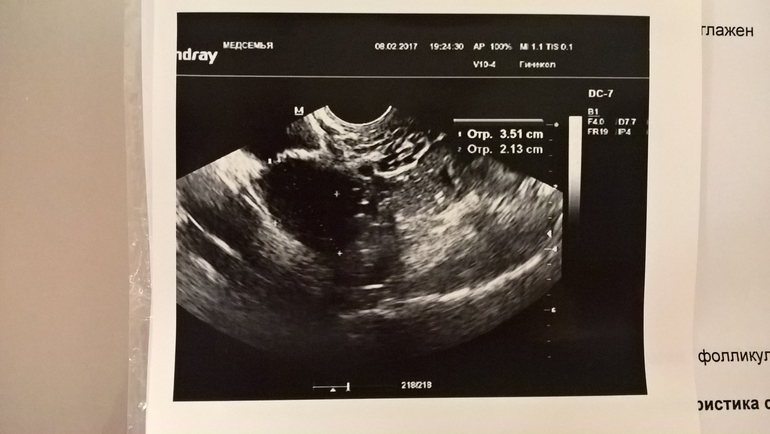

Не проходите мимо! На фото яичник, в котором 5 дней назад был дф 24 мм. Что вы видите сейчас??

Либо жт, либо не лопнувший. Края четкие, наверное, не лопнул🤔

Если жидкости нет,то это киста(( размерами на фоллик уже непохож...